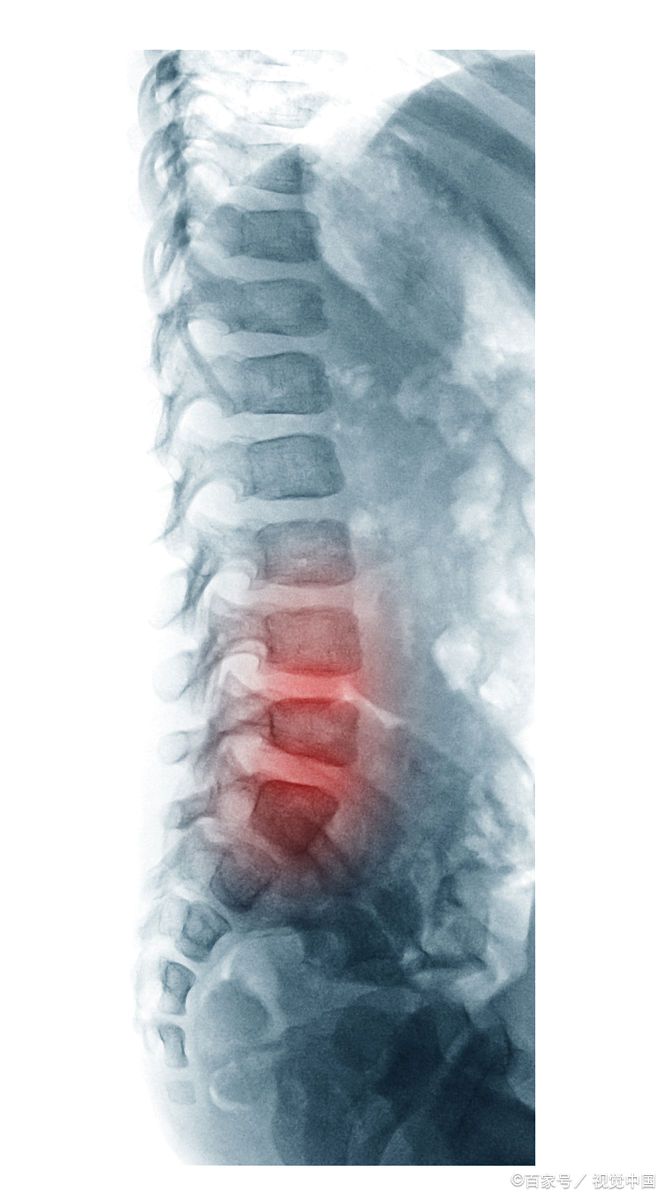

我看她带来的检查结果,腰4/5和骶1椎间盘有突出,属于中度病情,虽然有狭窄,但并不是主要原因,症状主要是臀部、大腿后方及小腿放射性疼痛,疼起来有烧灼和刀割一样疼痛、麻木。我们说这种病,绝大多数病例是继发于坐骨神经局部及周围的病变,对坐骨神经刺激、压迫和损害造成的。